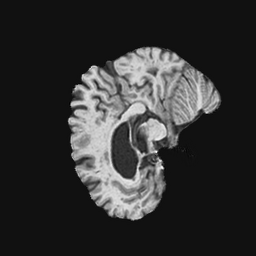

Exp. 1: Segmented adult brain data is used to evaluate our network’s regression performance with known ground truth Tisubscript𝑇𝑖T_{i}. 85 brains from the ADNI data set[1] were randomly selected; 70 brains for ΩtrainsubscriptΩ𝑡𝑟𝑎𝑖𝑛\Omega_{train} and 15 brains for ΩvalidationsubscriptΩ𝑣𝑎𝑙𝑖𝑑𝑎𝑡𝑖𝑜𝑛\Omega_{validation}. Fig. 2 shows an example slice of the ground truth and the reconstructed ΩΩ\Omega.

Figure 2: Example slice from the segmented adult brain MRI data set (a); reconstruction from 300 ωisubscript𝜔𝑖\omega_{i} based on SVRNet regression without SVR (b); SVR initialised with SVRNet predictions after eight iterations of SVR (c). Note that SVRNet (b) predicts individual slice transformations only from image intensities without any initial world co-ordinates of the sampled slice. (d) shows the achieved PSNR in dB when comparing the volumes of (b) and (c) to (a).

Reconstructing from Ti^^subscript𝑇𝑖\hat{T_{i}} initialisation without SVR yields a PSNR of 23.7 ±plus-or-minus\pm 1.09; with subsequent SVR the PSNR increases to 29.5±plus-or-minus\pm2.43 when tested on 15 randomly selected test volumes after four iterations of SVR.